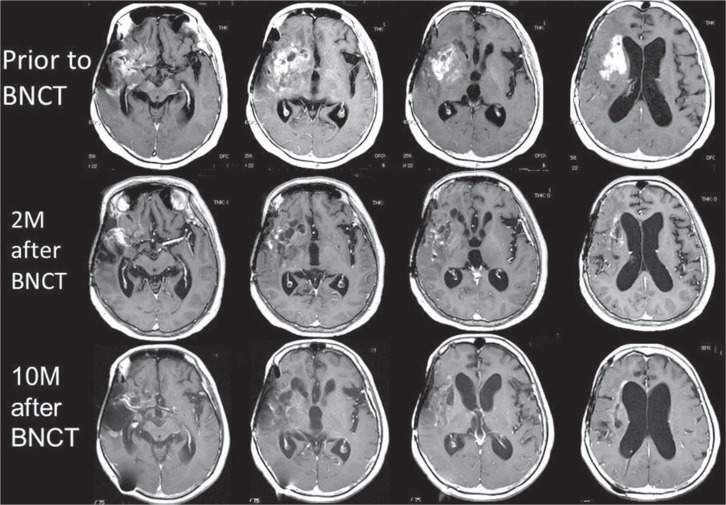

图2显示了一例复发性恶性胶质瘤的典型磁共振成像变化,该恶性胶质瘤由BNCT使用双酚a作为唯一的硼化合物进行治疗。最初的组织学是间变性寡星形细胞瘤,使用由X射线治疗(XRT)和替莫唑胺(TMZ)组成的标准化放疗进行化放疗后肿瘤复发。根据我们最近的复发恶性胶质瘤和脑膜瘤的治疗方案,该患者接受了BNCT治疗。简而言之,仅在中子辐照(100毫克/千克/小时)之前和期间的2小时内(200毫克/千克/小时)施用过双酚a。基于上述基于正电子发射断层扫描的模拟,我们选择了一个中子照射时间,将峰值脑剂量保持在12.0 Gy-Eq(灰度当量)以下。这里,Gy-Eq对应于对肿瘤和正常大脑具有同等效果的生物等效X射线剂量。图2显示肿块持续缩小超过1年,核磁共振成像无任何复发迹象。

图2:BNCT治疗的一例复发性恶性胶质瘤的典型磁共振改变。患者接受了开颅手术,组织学分析显示为间变性少枝-星形细胞瘤。她接受了多种化疗方案的化学照射,包括丙卡巴嗪、洛莫司汀、长春新碱和TMZ。不幸的是,肿块复发,左侧偏瘫加重。复发性恶性胶质瘤的RPA分类被判定为3级,因此估计复发时的中位生存期为3.8个月。BNCT之前的磁共振成像显示不规则增强的肿块从右侧额叶和颞叶浸润到基底神经节。BNCT之后,质量迅速而持续地缩小。BNCT手术一年后,病人没有接受任何化疗,情况良好。